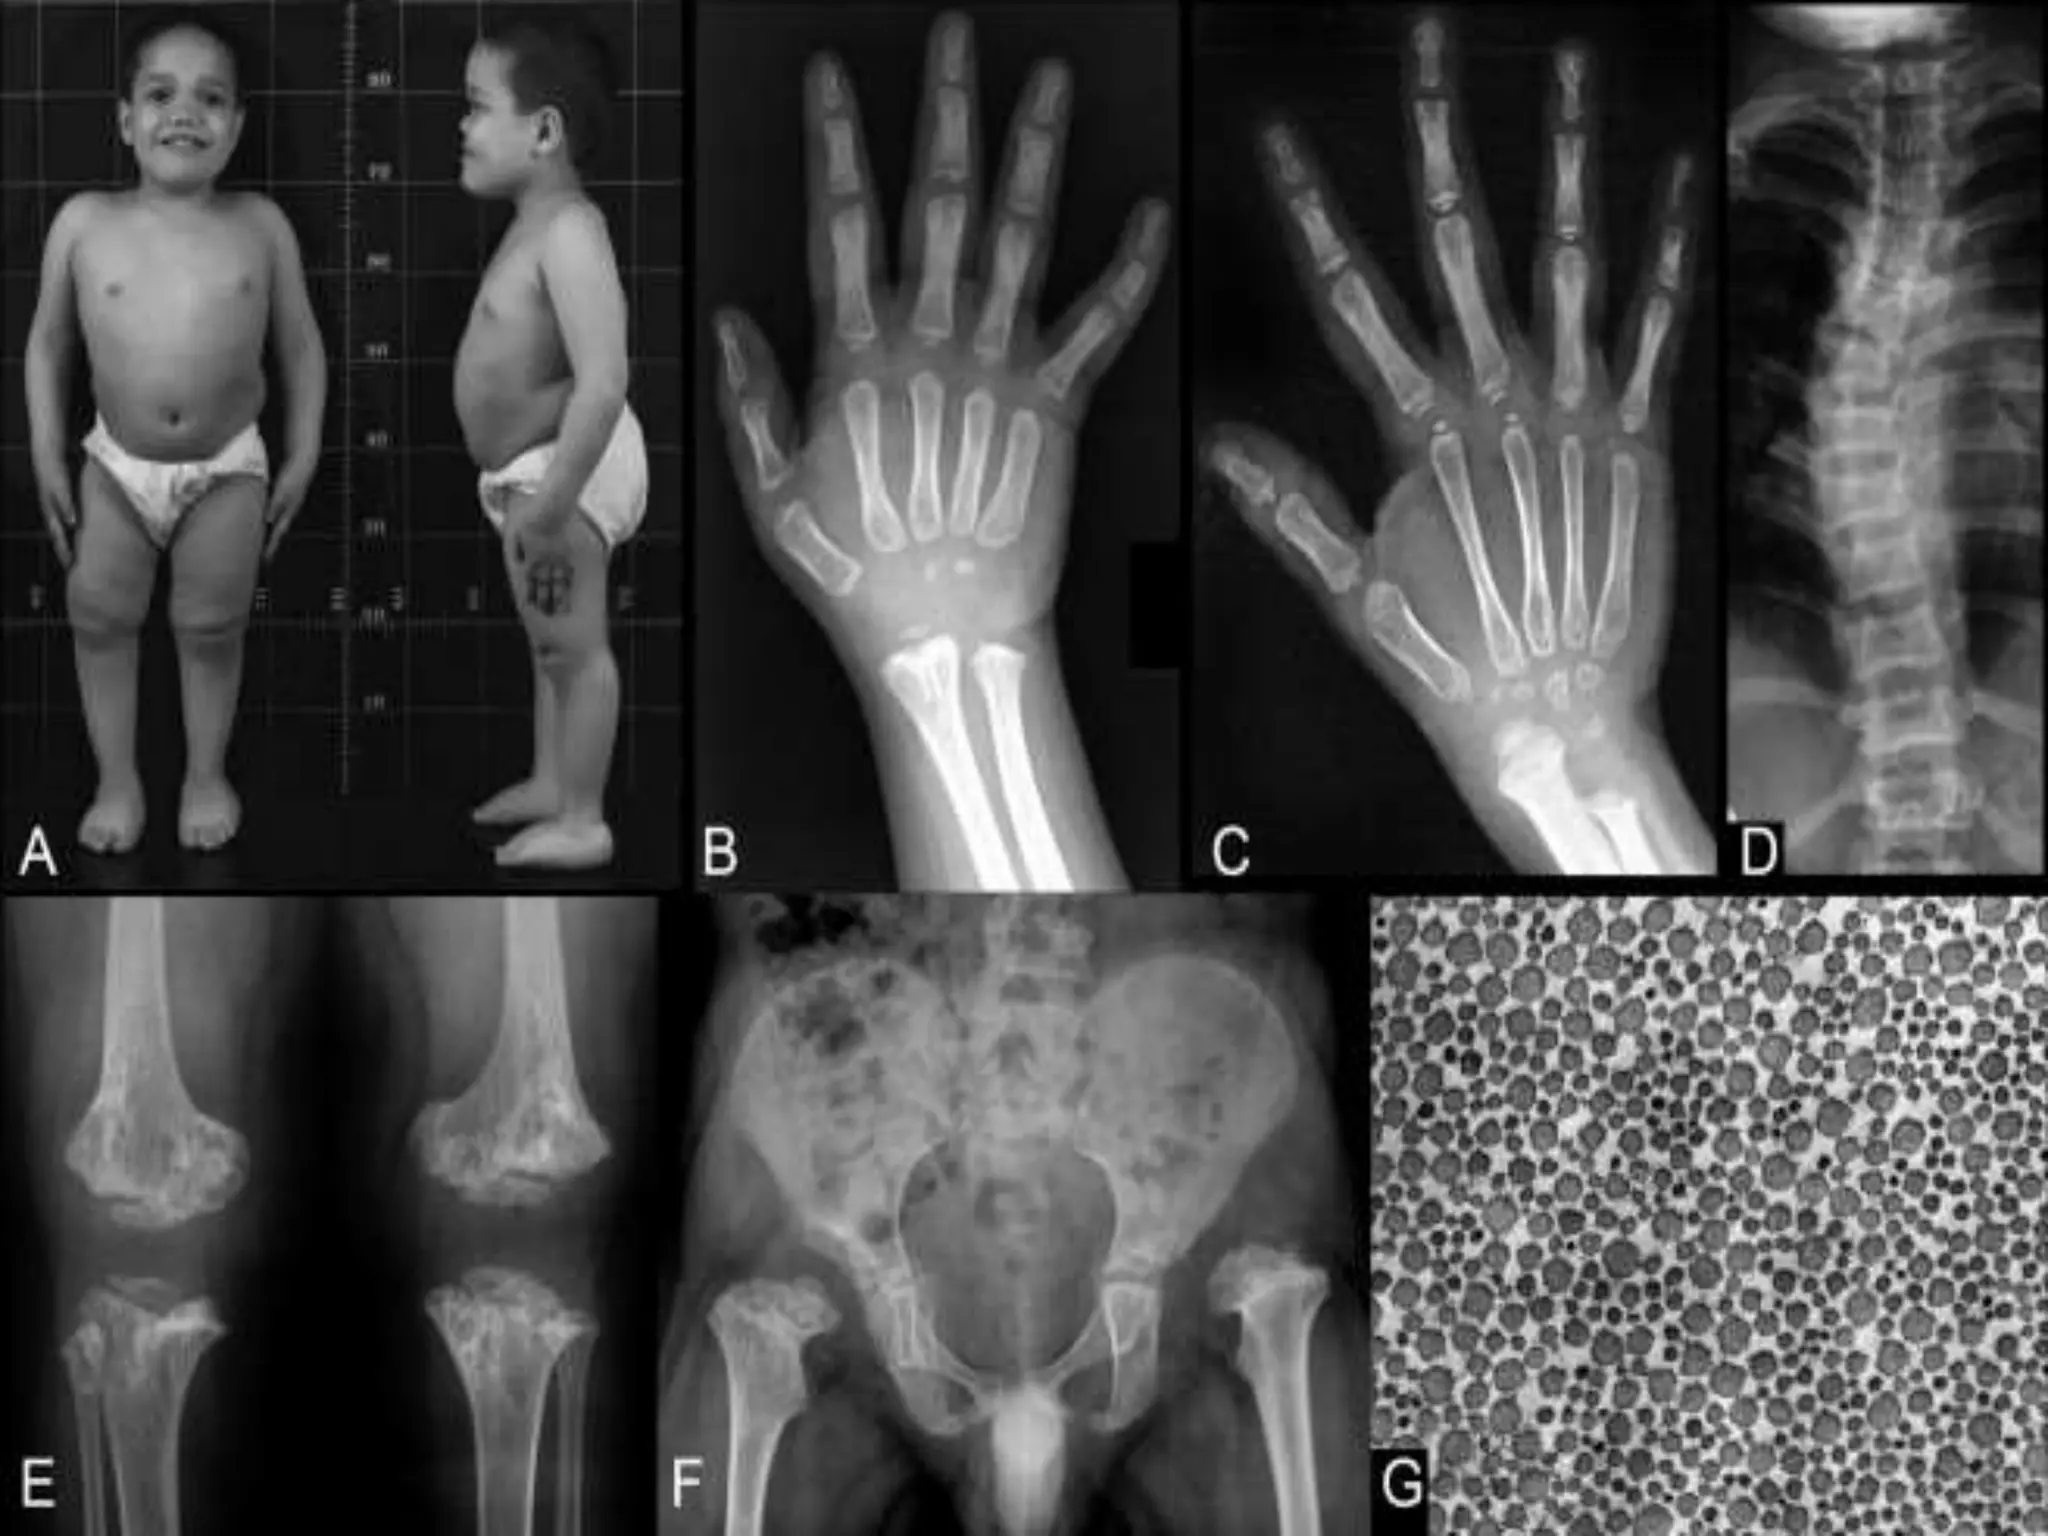

Metaphyseal chondrodysplasia (dysostosis)

Short limb dwarfism

Resembles rickets

Bilateral coxa vara

Bowed legs

Waddling gait

Deformities @ hip/knee

Sub types:

SCHMID

McKUSICK

JANSEN

SCHMID TYPE

CLASSICAL FEATURES (autosomal dominant)

McKUSICK TYPE (autosomal recessive)

Associated with sparse hair growth

JANSEN TYPE (RARE SPORADIC)

PRESENT WITH DEAFNESS